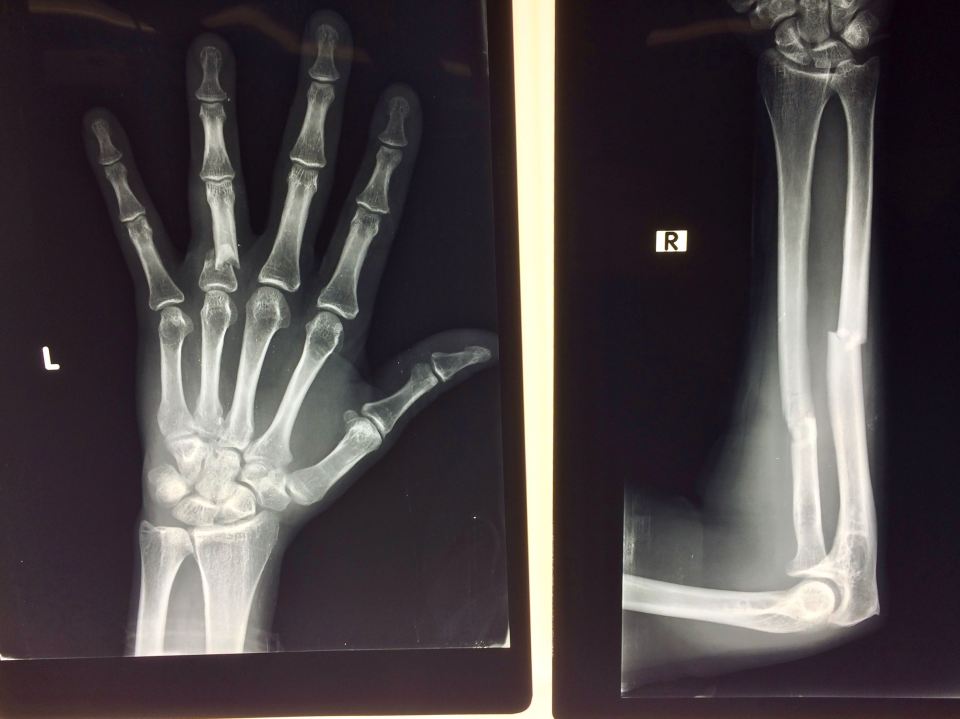

IMG_1135